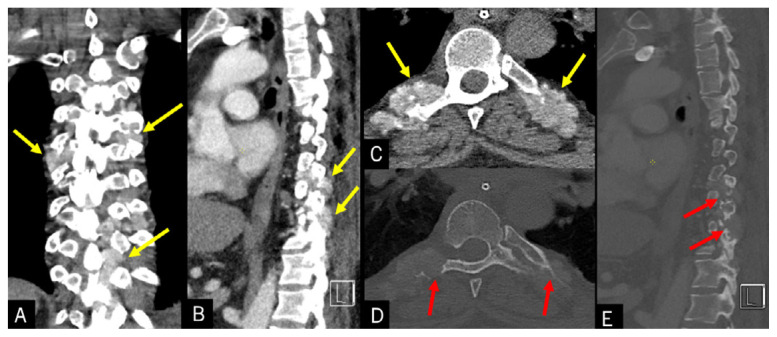

Tophaceous Gout in the Axial Skeleton: An Unusual Case with Key Imaging Characteristics.